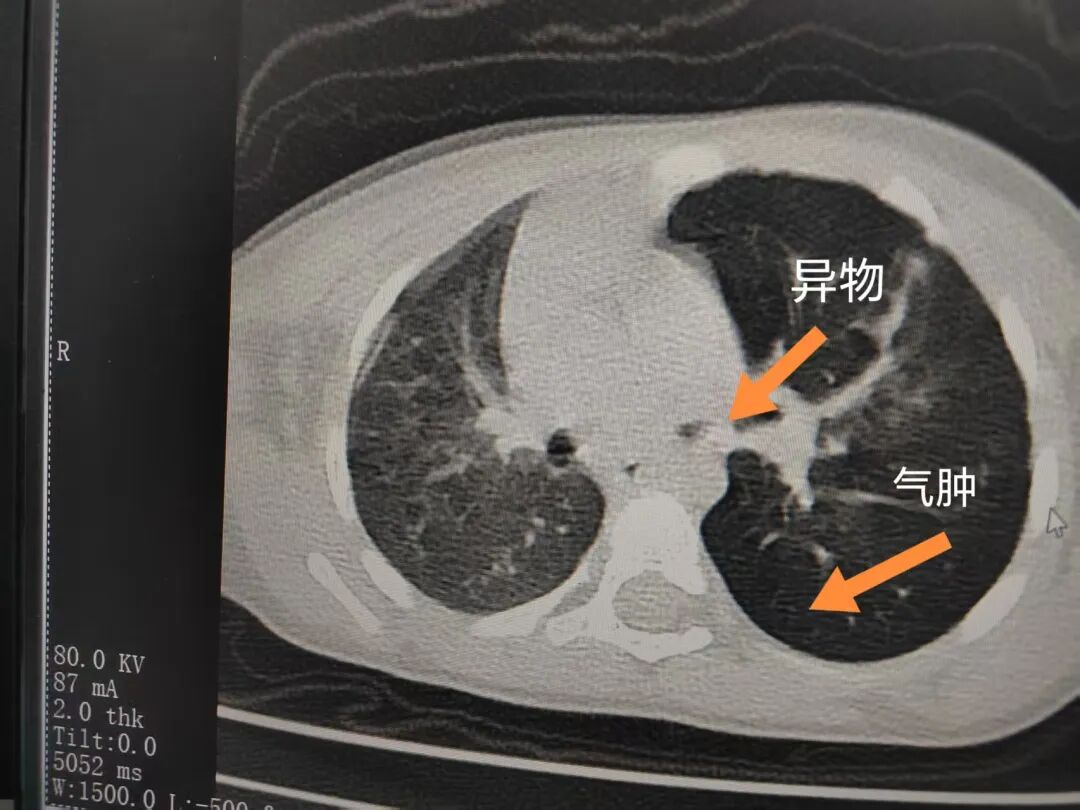

三天后(11月13日),趙寶出現(xiàn)高熱、咳喘加重,家長(zhǎng)著急了,再次帶他來(lái)到醫(yī)院。CT檢查顯示左肺過(guò)度充氣,左肺上下葉支氣管主干見(jiàn)不規(guī)則高密度影,左肺上葉可見(jiàn)大片狀密度增高影,縱隔窗實(shí)變,提示為“左側(cè)支氣管內(nèi)異物并繼發(fā)性改變,左肺上葉舌段肺膨脹不全”。

市二院小兒呼吸內(nèi)科副主任楊亞娟介紹,異物誤入氣道可能導(dǎo)致氣道阻塞,嚴(yán)重時(shí)可引發(fā)窒息,甚至危及生命。若異物進(jìn)入支氣管,造成不完全堵塞,可引起阻塞性肺氣腫;如完全堵塞支氣管,則可能導(dǎo)致肺組織萎縮,形成肺不張。此外,若異物存留時(shí)間較長(zhǎng),或?yàn)橹参镄援愇铮菀缀喜⒓?xì)菌感染,產(chǎn)生膿性分泌物,進(jìn)而發(fā)展為肺炎。她強(qiáng)調(diào),盡早診斷并取出異物,是減少并發(fā)癥、降低病死率的關(guān)鍵。